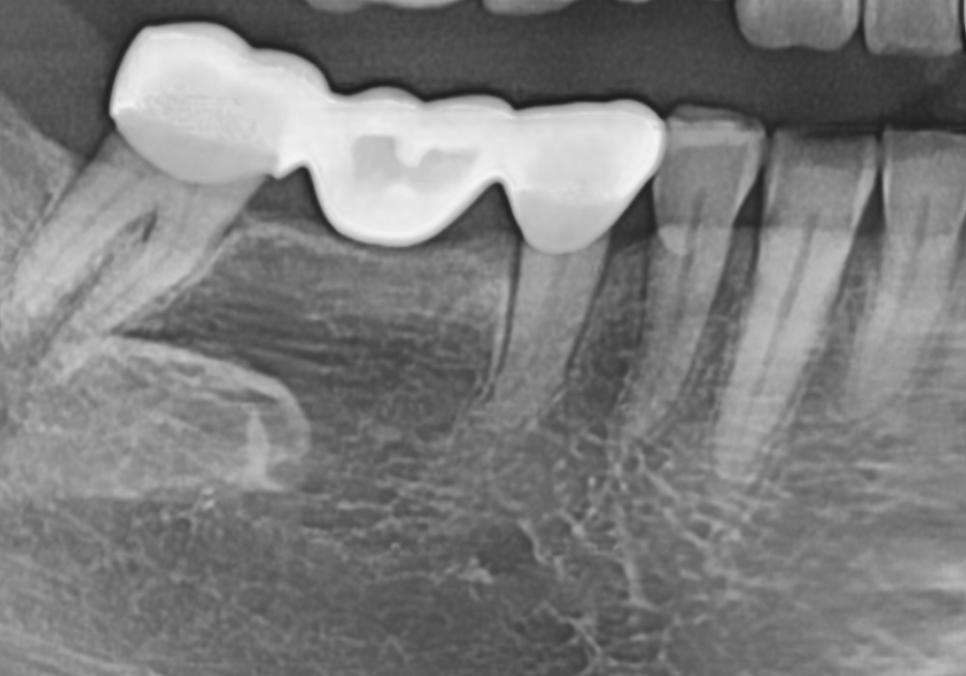

오른쪽 아래는 수직 파절로 인해

치아 금이 쫙 가 있었는데요.

방사선 사진을 살펴볼게요~

매끈해보여야 할 치아 뿌리 쪽에

돌기처럼 무언가 붙어있는게 보이시나요?

251201

바로 치석인데요.

사실 치석은 밀도가 낮아

방사선 사진상에는

잘 나타나지 않는 경우가 많아요.

그런데 만약 엑스레이 사진에서

이처럼 치아 옆면이 매끄럽지 않고

돌기처럼 튀어나온 것이 보인다면,

정상적인 잇몸 상태 , 치아 뿌리 면이 매끄러움

치은연하치석이 뿌리면에 돌기처럼 붙어있는 모습

그건 치석이 이미 엄청나게

두껍고 단단하게 쌓였다는 뜻이에요..ㅜㅜ